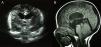

A) Corte coronal de la ecografía transfontanelar con dilatación del primer, segundo y tercer ventrículos. B) TC de cráneo (T1) con hidrocefalia obstructiva por estenosis congénita del acueducto de Silvio, fosa posterior y cuarto ventrículo pequeños, y herniación de las amígdalas cerebelosas (malformación Arnold-Chiari tipo 1).

La asociación VACTERL, uno de los patrones más comunes de malformación humana, comprende 3 a 7 malformaciones primarias de etiología desconocida y afectan vértebras, ano, corazón, tráquea, esófago, riñones y extremidades (del inglés «limbs»)1. Los pacientes con las anomalías típicas VACTERL pero con hidrocefalia parecen formar un grupo distinto en fenotipo y genética; esta entidad patológica se ha denominado asociación VACTERL-H (OMIM #276950) y se ha transmitido en algunas familias con un patrón de herencia autosómico recesivo o ligado al cromosoma X2-7. Mutaciones en los genes PTEN y ZIC3 han sido descritas como factores etiológicos para el desarrollo de la asociación VACTERL-H2,5. Los pacientes con esta asociación usualmente presentan anomalías simétricas del rayo radial, renales, anales, genitales y cardiacas4; otras anomalías son excepcionales6-8. Se describe aquí el caso de un infante con la asociación VACTERL-H y agenesia tibial. Se trata de un paciente masculino, de 23 meses de edad, obtenido del tercer embarazo a término. El padre y la madre (ambos de 33 años al nacimiento del propositus) niegan consanguinidad, antecedentes patológicos, exposición a mutágenos o teratógenos e historia de familiares afectados. Hubo control prenatal, el cual inició en la sexta semana de gestación y no se presentaron complicaciones obstétricas. El embarazo se resolvió por parto vaginal a la 38.a semana. Al nacimiento, el paciente presentó un Apgar 8/9, peso de 3.000g (percentil 25-50), talla de 48cm (percentil 25) y perímetro cefálico de 39,5cm (percentil > 97). La exploración física reveló dolicocefalia con fontanelas amplias y normotensas; hubo incapacidad para introducir la sonda nasogástrica a través del esófago y el estudio radiológico mostró atresia esofágica con fístula traqueoesofágica. Así mismo, se observó la extremidad inferior izquierda con acortamiento de la pierna y pie en varo con polidactilia preaxial de 8 dedos, columna vertebral con desviación dorso-lumbar y ano imperforado; no hubo dismorfia facial ni anomalías en las otras extremidades ni en los genitales. Se practicaron una esofagoplastia y una colostomía de descarga dentro de las primeras 48h de vida extrauterina. El estudio radiológico detectó escoliosis dorso-lumbar, fusión costal (tercera con cuarta y quinta con sexta), así como 13 costillas en el hemitórax derecho, fusión costal (tercera con cuarta y novena con décima) sin costilla accesoria en el hemitórax izquierdo, falla múltiple hemivertebral de T4 a T7, T9 a T12 y en vértebras lumbares (fig. 1A). La radiografía anteroposterior de la extremidad inferior izquierda mostró ausencia de la tibia y presencia de 8 dedos con primer metatarsiano ausente e hipoplasia de las falanges del primer dedo; hubo además hipoplasia del tercer metatarsiano visible y ausencia de la falange terminal del cuarto dedo (fig. 1B). La ecografía transfontanelar detectó dilatación del primer, segundo y tercer ventrículos (fig. 2A) mientras que la TAC de cráneo demostró hidrocefalia obstructiva por estenosis congénita del acueducto de Silvio, fosa posterior y cuarto ventrículo pequeños, y herniación de las amígdalas cerebelosas, datos compatibles con la malformación Arnold-Chiari tipo 1 (fig. 2B). La ecografía renal evidenció riñón derecho único, mientras que la ecocardiografía fue normal. Por otra parte, se realizó un cariotipo de alta resolución (> 550 bandas) y un estudio de fragilidad cromosómica que resultaron normales. A pesar del cuadro malformativo aquí descrito, el paciente ha tenido una evolución favorable. Las malformaciones en vértebras, ano, esófago, riñones y extremidades, aunadas a la hidrocefalia, permitieron integrar el diagnóstico de asociación VACTERL-H3. Aunque la agenesia tibial ha sido descrita en la asociación VACTERL9,10, no había sido reportada en la asociación VACTERL-H. Por otra parte, existe el reporte de un caso con asociación VACTERL-H, con 13 pares de costillas5; en el presente paciente, se observaron 13 costillas en el hemitórax derecho y fusión de costal en ambos hemitórax (fig. 1A), lo que sugiere que el espectro de malformaciones en la asociación VACTERL-H es más amplio de lo que se ha reconocido con anterioridad. La ausencia de aberraciones y roturas cromosómicas espontáneas, excluyó las trisomías 13 y 18, así como la anemia de Fanconi4,7,8. Es evidente que el análisis molecular de alto rendimiento (como el arreglo de hibridación genómica comparativa y la secuenciación genómica) y el estudio de la expresión génica en estos pacientes permitirán precisar los mecanismos moleculares causantes de esta afección poco comprendida. La evolución favorable, la supervivencia inusual y la agenesia tibial de este paciente representan una expansión de la asociación VACTERL-H.